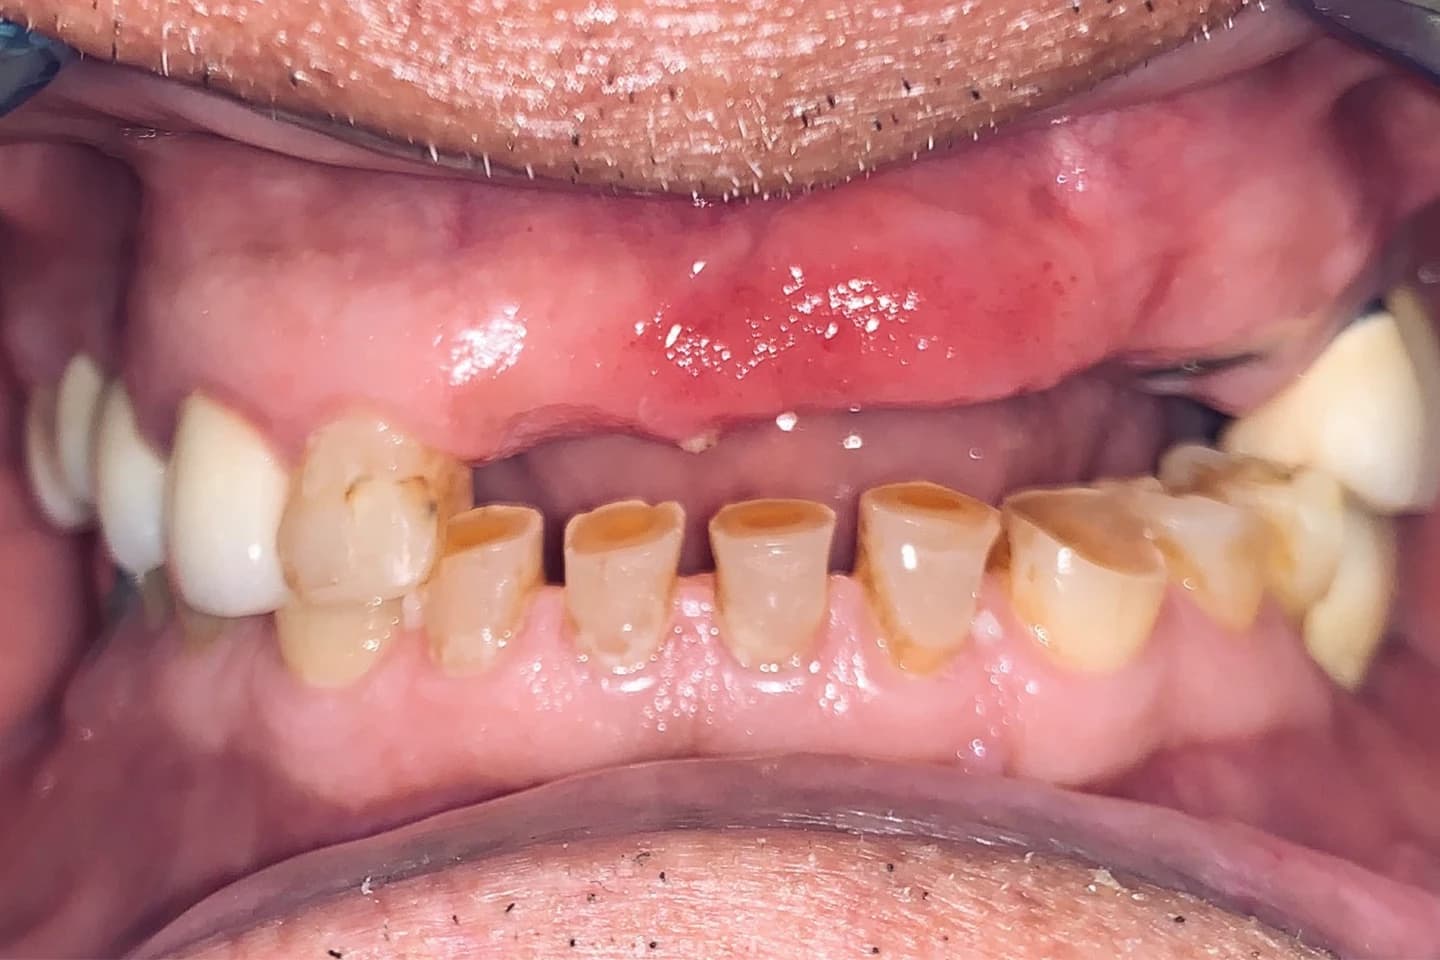

Krunice za zube - pre i posle

- Pogledajte kako krunice mogu da zaštite i obnove oštećenost kada su u pitanju zubi, vraćajući im estetiku i funkciju. Galerija radova će vas inspirisati da i vi transformišete svoj osmeh.